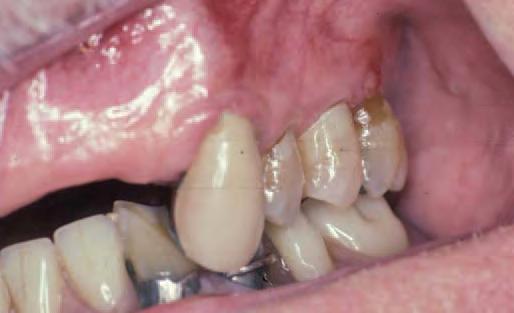

Issuu converts static files into: digital portfolios, online yearbooks, online catalogs, digital photo albums and more. Sign up and create your flipbook.